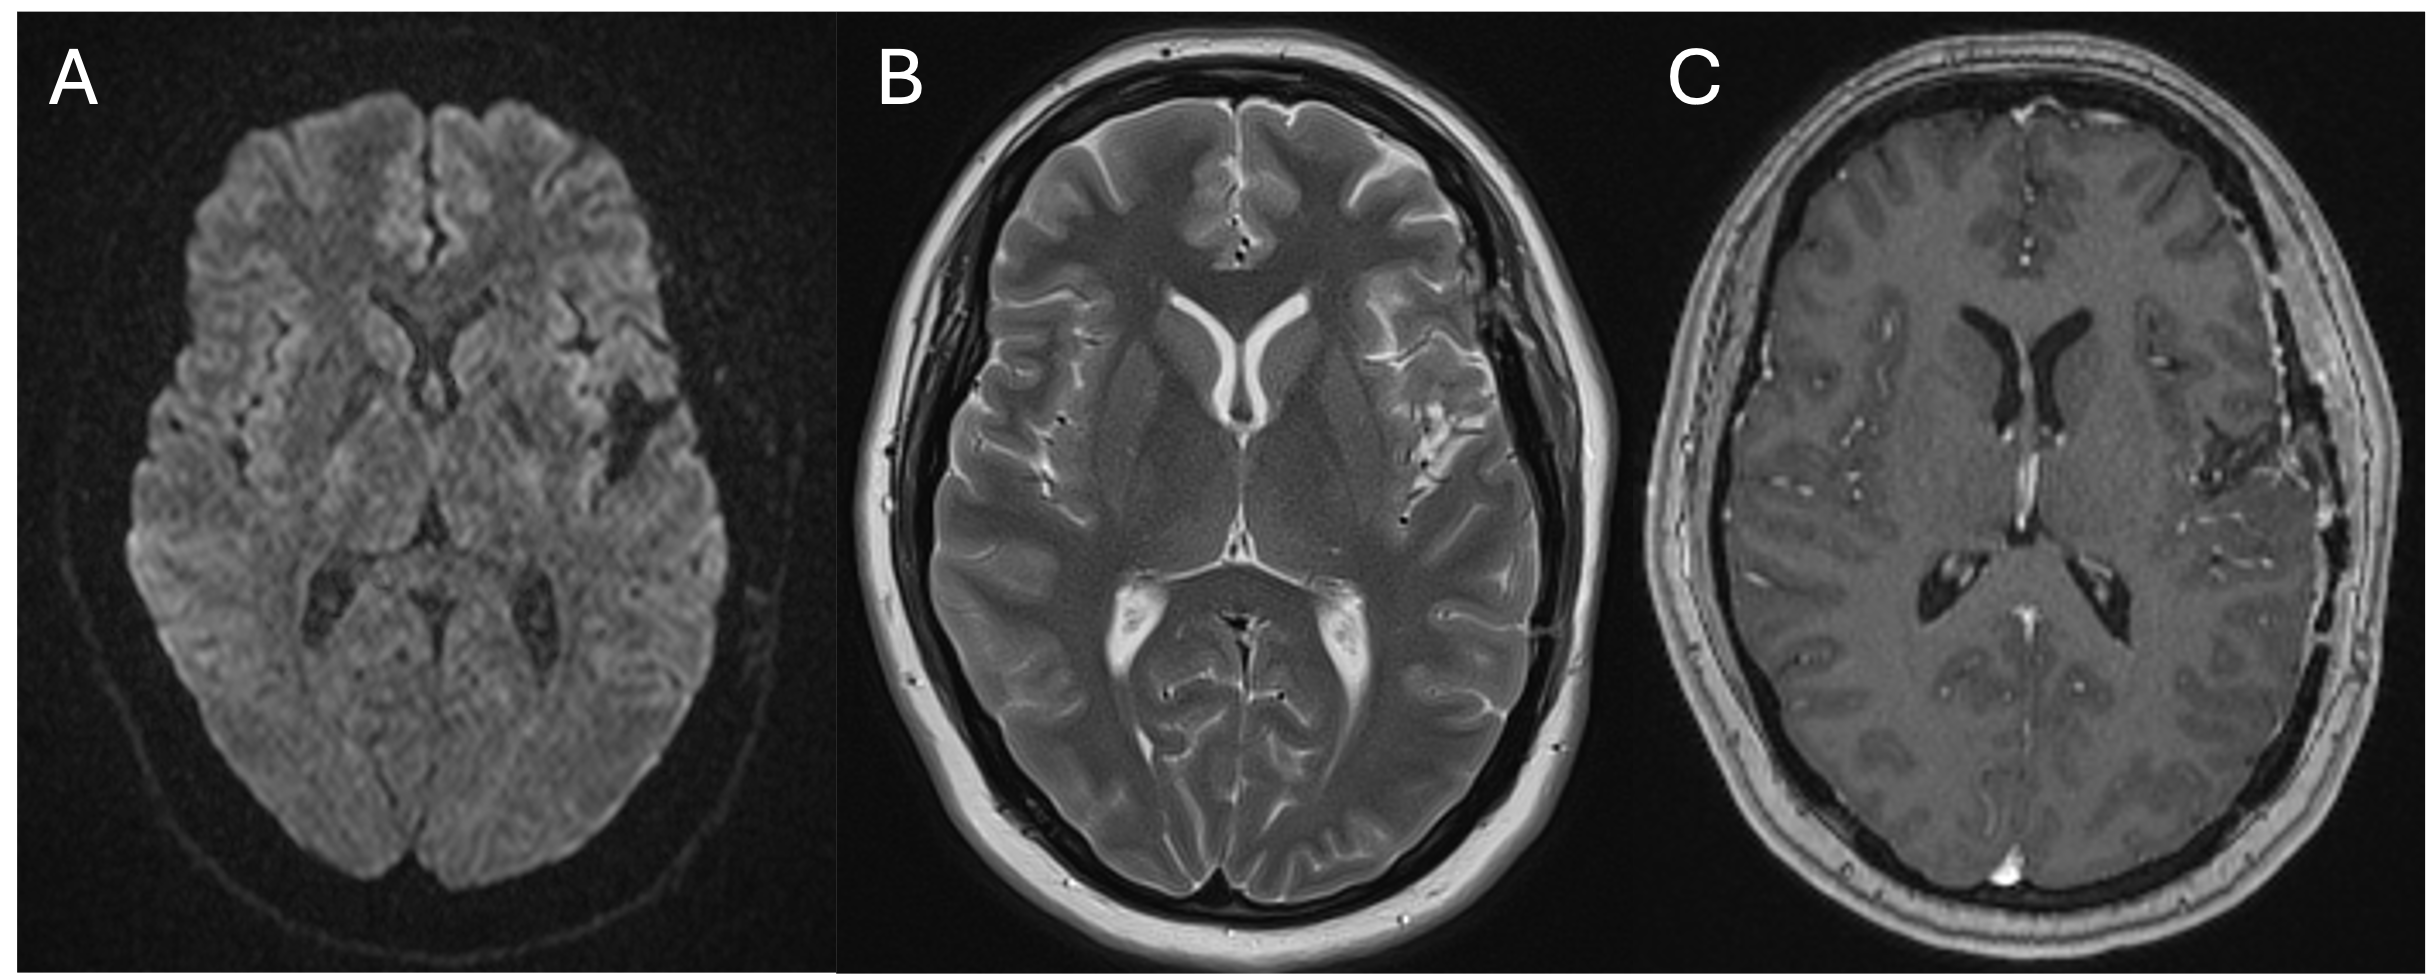

Results

Picture1

Figure 1. PRE > MID. Paired grey matter (GM) CVR difference map expressed in t-values (paired t-test; n=16; p<0.05). Significant decreases in CVR are shown in the left putamen and bilaterally in the cingulate and paracingulate gyrus. Images are in MNI space.

Figure 2. Average (A) PRE (n=18), (B) MID (n=18), and (C) POST (n=16) GM CBF expressed in mL/100g/min. Images are in MNI space.

Discussion

• Our results demonstrate that nonconcussive head impacts may lead to decreased CVR and possibly increased CBF, suggesting vascular dysfunction2 and compensatory hyperemia7

• These metrics show promise as early biomarkers of trauma-related brain changes in contact sports. Longitudinal studies should assess long-term consequences of observed CBF/CVR change